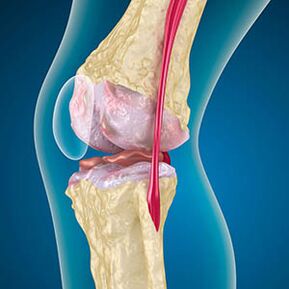

Z artrozo je hrustanec, ki obloži robove kosti, abrazijska ali popolnoma odsotna. Poškodovano tkivo ni vir bolečine, ker nima receptorjev. Vnetje v bližnjih strukturah povzroča značilne simptome.

Telo nadaljuje regeneracijo poškodovanih tkiv, vendar hrustanec raste neenakomerno. Kot rezultat tega se tvorijo nepravilnosti, ki poškodujejo druge elemente sklepa. Narava osteofitov je razložena s kompenzacijo za gladek skupni hrustanec. Druga različica kaže, da je rast "Spursov" Povezana je s poskusom stabilizacije sklepa medialno ali stranske zaradi oslabitve mišic.